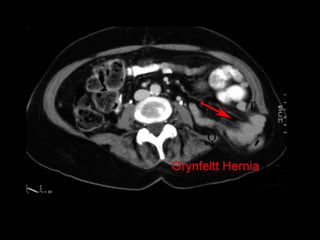

Hernias lumbares

• -2%

Congénitas 10%

Grynfelt : Tríangulo superior de la región lumbar

Métodos diagnósticos

• En pacientes muy obesos y con sacos herniarios

muy pequeños.

• USG dinámico, en reposo y con maniobra de

valsalva

• TAC dinámica

• RMN

• Electromiografía de la musculatura abdominal: El

pronóstico de la plastía es malo si se encuentra

una lesión nerviosa asociada, por dilatación

posterior de los músculos denervados lo cual

ocasionará recidiva